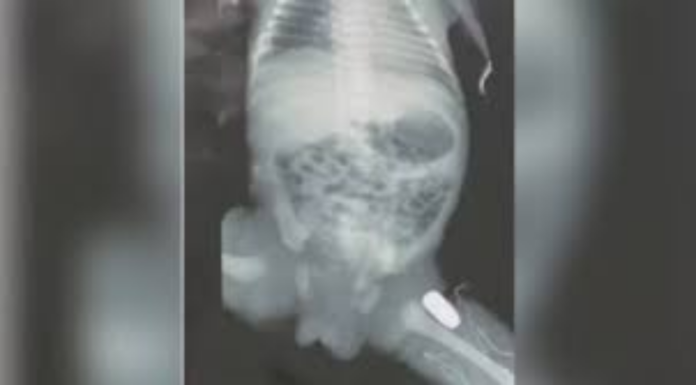

A condição da mãe é estável, e o bebê passará por uma cirurgia para remover o projétil que ficou alojado na perna.